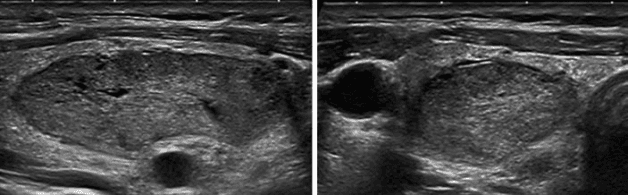

Siêu âm để phát hiện u tuyến giáp đang ở mức độ TIRADS nào

Hình ảnh siêu âm u tuyến giáp TIRADS 4